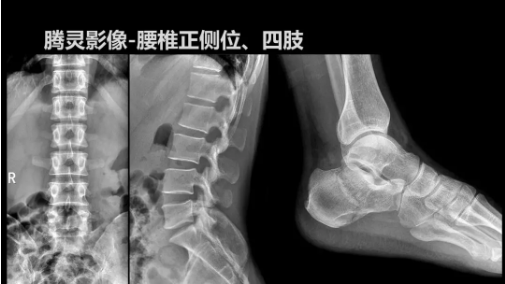

“騰靈”是安健科技的第四代動態(tài)DR產(chǎn)品,可實(shí)現(xiàn)全科室應(yīng)用。如各類常規(guī)的X線檢查、消化道檢查、骨科檢查、婦科、兒科檢查等。此外,安健科技為“騰靈”在真正意義上實(shí)現(xiàn)多科室、多功能診斷進(jìn)行了多項(xiàng)針對性設(shè)計。

相較前代產(chǎn)品,“騰靈”在圖像質(zhì)量方面得到了全面升級,“騰靈”采用17*17非晶硅平板探測器設(shè)計,采集矩陣達(dá)3072*3072,動態(tài)范圍達(dá)16bit,為成像提供超大視野的同時保證成像質(zhì)量,此外,該款機(jī)型可根據(jù)醫(yī)療機(jī)構(gòu)的差異化需求而選配不同的動態(tài)平板探測器,以此來適應(yīng)不同階層用戶所需。